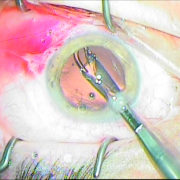

ιριδικής στήριξης

καταρράκτης με τραυματική

ρήξη οπ.περιφάκιου από

έγγχυση ANTIVGEF παράγοντα

του οπ. περιφάκιου

Sun Set Syndrome

πίσω από την ίριδα

ζώνης 5 ωρών

φακού